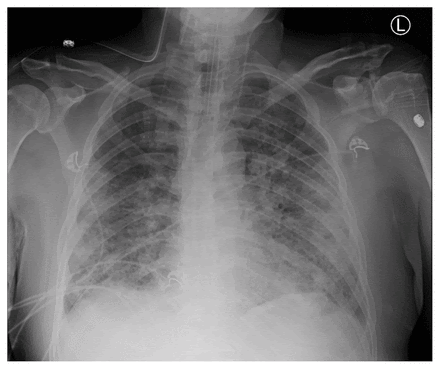

| Is Chronic Bronchitis Contagious? What You Need to Know - Verywell Health Posted: 11 Mar 2021 12:00 AM PST ![]() Chronic bronchitis is one of the two main types of chronic obstructive lung disease (COPD). The other is emphysema. Most people with COPD have symptoms of both conditions. In chronic bronchitis, swollen airways and excessive mucus production cause a chronic cough and difficulty breathing. Many people hear the persistent cough associated with chronic bronchitis and wonder if it is contagious. Over 16 million people have been diagnosed with COPD in the United States. Of these, over 3.8 million were diagnosed with emphysema, and nine million were diagnosed with chronic bronchitis. Chronic inflammation in the bronchi, airway obstruction, and chronic mucus production cause changes throughout the lungs. Many people who have chronic bronchitis eventually develop emphysema as well. twinsterphoto / Getty Images Acute vs. Chronic BronchitisBronchitis is an inflammation of the bronchi, branching tubes going into the lungs. These tubes carry air to and from the lungs. When the bronchial tubes become inflamed and swollen, less air can pass through them. Inflammation causes increased mucus production, which leads to an irritating cough when trying to clear the mucus. The inflammation may last a short period after an upper respiratory infection or may be chronic. Acute bronchitis usually develops after a cold or upper respiratory infection, and it improves within a few days without residual effects. Chronic bronchitis is more serious and develops slowly over time, sometimes months or even years. Because the symptoms of chronic bronchitis develop so slowly, many people do not notice how bad their symptoms have become. Acute bronchitis usually starts with a runny nose, sore throat, chills, and low-grade fever. As the infection moves from the nose and throat into the lungs, a dry cough usually develops. The bronchi become inflamed and mucus production is increased. At this point, you may notice a productive cough, wheezing, and chest tightness. In acute bronchitis, these symptoms are limited to no more than three weeks. Those with chronic bronchitis usually have a persistent cough and are frequently smokers. Smoking damages the cilia, tiny whip-like structures that beat dust and dirt out of the airway. Chronic bronchitis may develop after multiple episodes of acute bronchitis. Acute Bronchitis

Chronic Bronchitis Generally Isn't ContagiousChronic bronchitis is an inflammation of the airways usually found in people with a long history of smoking, exposure to environmental chemicals, or genetic predisposition. Even though you may have a productive cough with chronic bronchitis, you are not contagious. The cough is secondary to mucus production and airway irritation, not a viral or bacterial infection. Increased mucus and inflammation can increase the risk of a secondary infection. If you have chronic bronchitis and have a sudden worsening of symptoms, fever, increased sputum production, or discoloration of the sputum, you may have developed a secondary infection. A secondary infection with a virus or bacteria is contagious, and it can be passed from person to person. Chronic bronchitis is not contagious unless there is a secondary infection. The chronic cough and mucus production characteristic of this disease may seem similar to pneumonia or other respiratory infection, but it is not the same. Preventing InfectionsVaccinesInfluenza A and B, parainfluenza, respiratory syncytial virus, and coronavirus are the most common viral causes of secondary lung infections. Getting an annual flu shot can help prevent secondary infections from influenza viruses, as can avoiding people who are ill. The viruses that cause influenza vary each year, so it is essential to get the influenza vaccine yearly. Schedule your influenza vaccine between October and December, so you are protected for the entire influenza season (in the Northern Hemisphere). Ensure all of your vaccines are up-to-date to minimize your risk of catching preventable respiratory infections. Verify whether you are a candidate for a pneumococcal vaccine. The pneumococcal vaccine is recommended for all adults 65 years and older and adults younger than age 65 with certain health conditions, including lung disease. Follow up with your healthcare providers regularly so any secondary infections can be detected early. Lifestyle ChangesPractice good hand hygiene, avoid crowded areas and ones with poor ventilation. To keep lung secretions thinner and easier to handle, drink lots of fluids and use a humidifier or vaporizer if it eases symptoms. If you are a smoker, seek help to quit. Avoid being around secondhand smoke and air pollution. There are medications for nicotine replacement that have helped many smokers quit. Counseling and support groups may also help. Take care of your overall health by getting as much exercise as you can tolerate. Eat healthy, well-balanced meals. Get plenty of rest and sleep. Stress causes changes in hormone levels in the body. These changes can make chronic conditions worse. If possible, decrease stress using deep breathing or relaxation exercises. A Word From VerywellChronic diseases can be hard to manage. It can be discouraging when you have a relapse and symptoms worsen, but there are many steps you can take to minimize the risk of worsening disease. Seek help if you are a smoker. There are many therapy options available to help you quit. Focus on your health by ensuring you get exercise, eat healthily, and get plenty of sleep. Advise family members and friends of your condition so they understand that your cough is not contagious, but you are at increased risk for secondary infections, which are contagious. Ask them to let you know if they may be ill so you can protect your health. Follow all of your healthcare provider's instructions on medications to minimize your symptoms and improve your overall health. Finally, do not hesitate to seek help if managing your symptoms is emotionally overwhelming. |